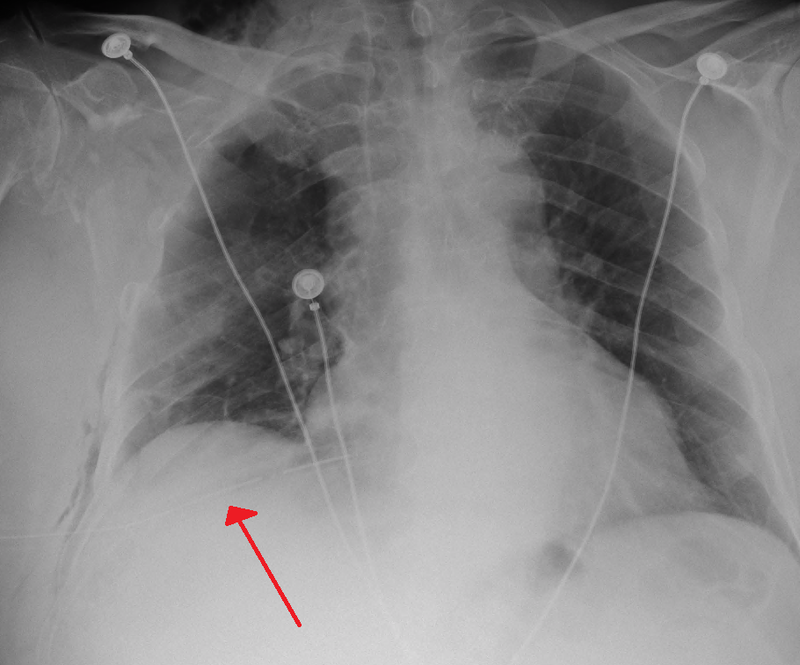

Pneumothorax

Pneumothorax is air buildup in the pleural space.

Pneumothorax leads to collapse of a portion of the lung.

When there is a penetrating chest wound, tension pneumothorax develops.

Pneumothorax is a medical emergency.

Pneumothorax is treated by inserting a chest tube.